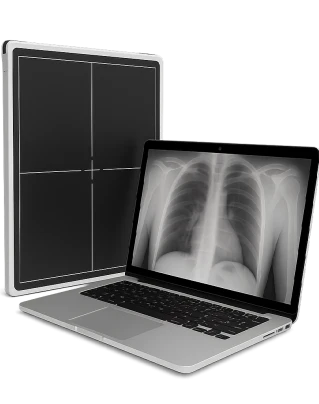

RTG kręgosłupa to nieinwazyjna metoda diagnostyczna, która z wykorzystaniem promieniowania rentgenowskiego pozwala zobrazować kości, stawy oraz krążki międzykręgowe w celu oceny stanu kręgosłupa i wykrycia zmian patologicznych.

Zdjęcie RTG pokazuje wzajemne położenie struktur kostnych, stan krążków międzykręgowych oraz kontury powierzchni stawowych. W razie potrzeby lekarz wykonuje zdjęcia z próbami czynnościowymi w celu oceny ruchomości i stopnia niestabilności segmentu kręgosłupa.